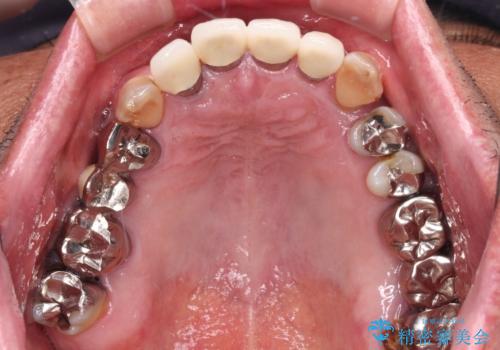

- 奥歯が咬みにくく、前歯がぐらぐらするとのことで来院された患者様です。

咬合力が強く、奥歯が欠損している状態でした。

欠損部はインプラントによる補綴治療を行うこととし、臼歯部が安定した後に、上下前歯部をオールセラミッククラウンにて補綴治療を行うこととしました。